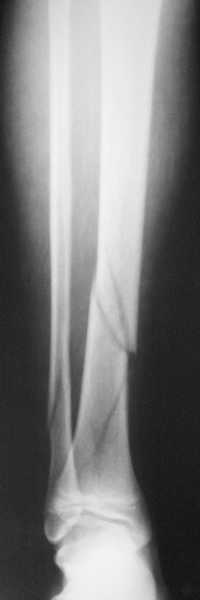

В приложении метафизарный перелом у ребёнка 14лет, с распространением линии перелома на зону роста.

В примере показан не перелом пилона, а эпифизеолиз, м/берцовую кость сознательно не фиксировал(длина её восстановлена, ротации нет),у детей стараемся минимизировать операц.травму, несколько позже разрешил полную нагрузку на ногу(4 недели). Но принцип фиксации б/берцовой кости м.б. таким же.